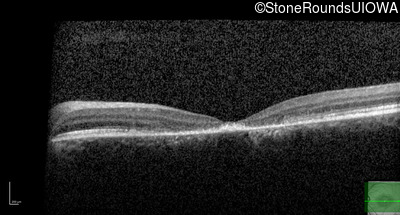

Optical Coherence Tomography - Left - 10/125 -1

Exemplar / OCT Stack